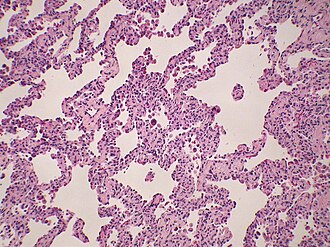

|

NSIP. H&E stain. | |

Microscopic

Features:[2]

- Diffuse fibrosis:

- Uniform fibrosis (unlike UIP).

- "Linear fibrosis" has a good prognosis - should be mentioned in the report.

- Linear fibrosis = fibrosis that follows alveolar walls + no architectural distortion.

- +/-Lymphoid nodules - association with collagen vascular disease. (???)

- +/-Focal organizing pneumonia.

Notes:

- Inflammation in NSIP usually more prominent than in UIP.

- No honeycombing - key difference between UIP and NSIP.